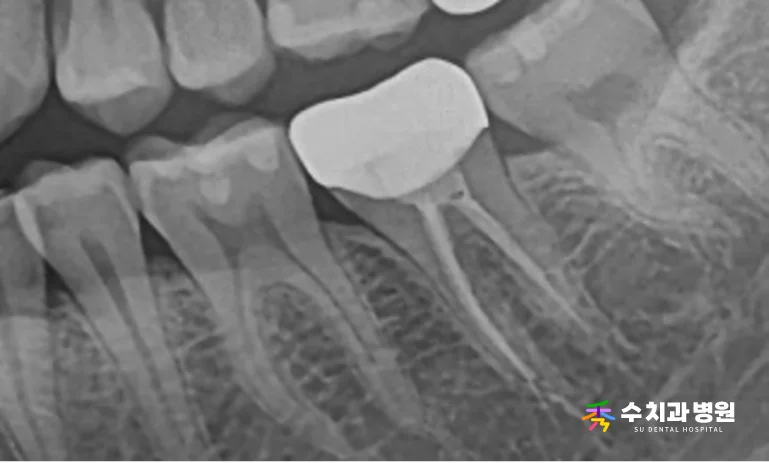

치료가 모두 끝난 후 방사선 사진을 확인해 보면,

신경치료가 뿌리 끝까지 꼼꼼하게

잘 마무리된 것을 볼 수 있습니다.

[📸 치료 후 엑스레이사진] (촬영일: 2024년 10월)

환자분께서 내원 당시 호소하셨던

씹을 때의 통증은 완전히 사라졌으며,

현재 일상생활에서 편안하게 식사하고 계십니다.